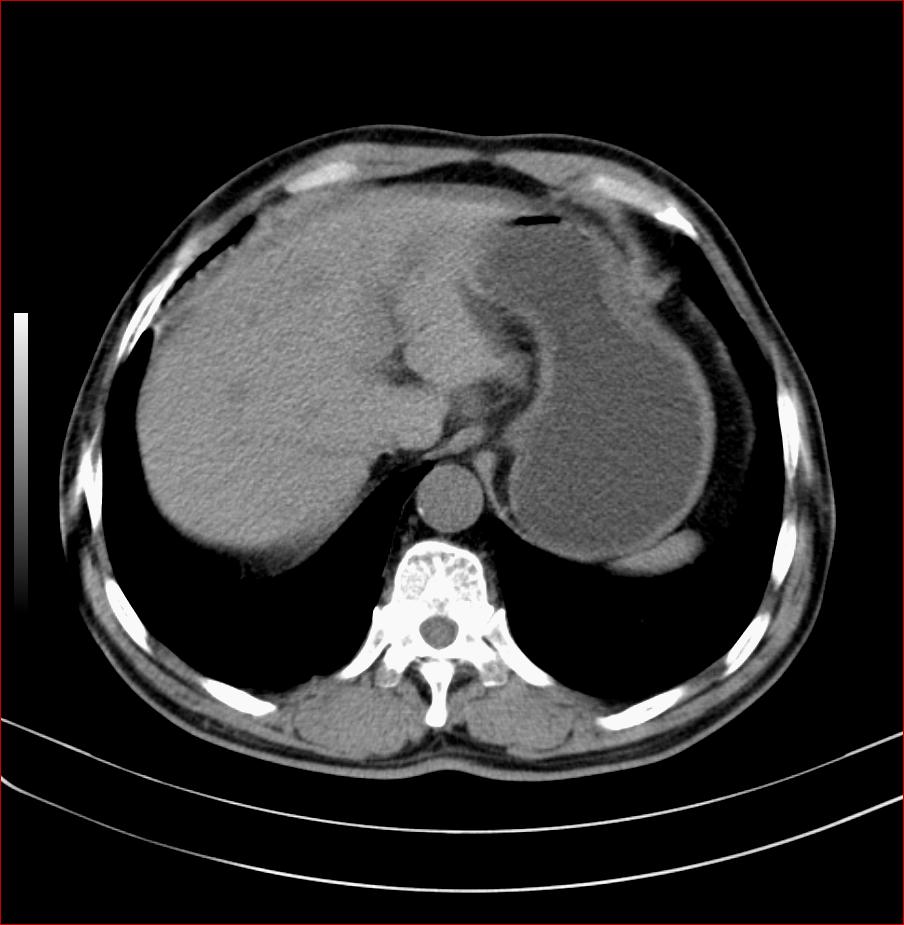

男性、63岁,上腹部不适月余,加重5天,疼痛,胰头体积增大,占位病变。胃体部胃壁增厚。

考虑胃淋巴瘤并小网膜及腹膜后淋巴结转移。

考虑胃癌并小网膜及腹膜后淋巴结转移。